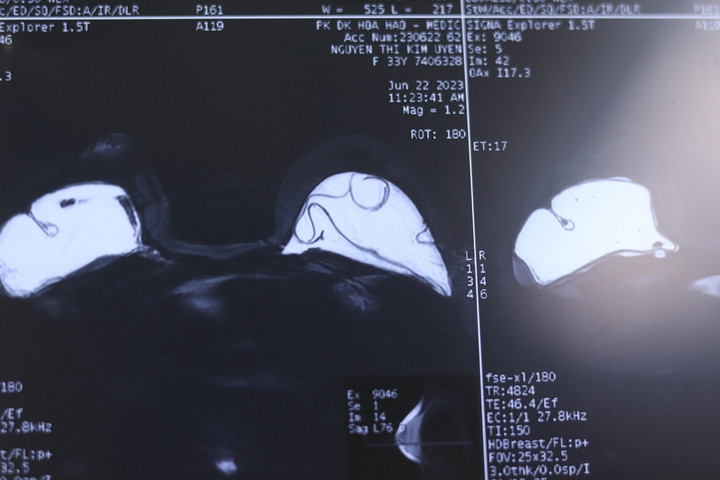

Vì sao cần chụp MRI trước phẫu thuật bóc bao xơ?

Chụp MRI nhũ chuyên sâu truớc khi tháo túi ngực và bóc bao xơ giúp kiểm tra tình trạng bệnh lý tuyến vú, bao xơ, pocket, các bệnh liên quan đến túi ngực, các u… (khuyến cáo chụp MRI thông thường, siêu âm, X-quang không mang lại hiệu quả với những trường hợp đặt túi ngực và vỡ túi ngực).

Sau đó, bác sĩ sẽ đánh giá tình trạng bao xơ, những bất thường trong và ngoài pocket và có phương pháp phẫu thuật tốt nhất cho khách hàng. Với những trường hợp bao xơ đôi, bóc tách khó khăn thời gian phẫu thuật kéo dài có thể lên đến 4 tiếng - bác sĩ tạo hình lại khoang đặt túi mới.

Với những hãng túi ngực lớn ở Mỹ, kết quả chụp MRI chuyên sâu về nhũ là một trong những yếu tố cần thiết giúp khách hàng được thay túi mới, nếu vẫn trong thời gian bảo hành.

Kết quả chụp MRI vỡ túi ngực và co thắt bao xơ.

Nhận được sự tư vấn không hợp lý chị quyết định chụp MRI nhũ chuyên sâu, với kết quả vỡ túi ngực, bao xơ, chị tìm đến Ths.BS Hồ Cao Vũ quyết định tháo túi ngực vỡ, bóc bao xơ và đặt lại túi ngực mới.